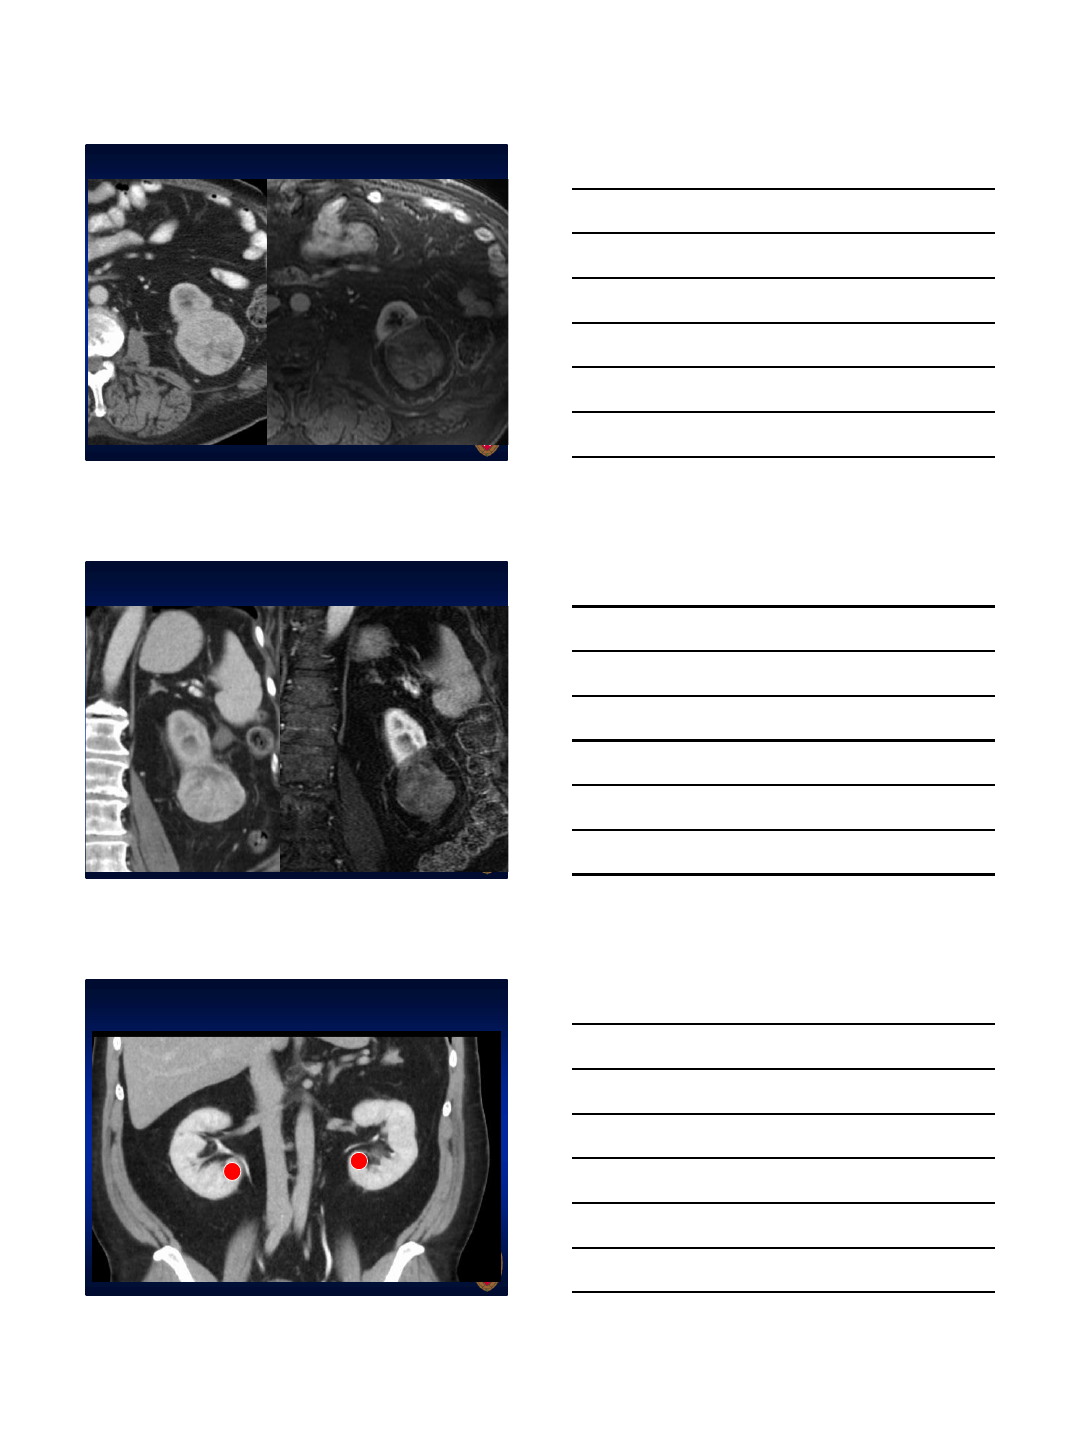

6.3 cm RCC: Pre-ablation scans

3 LK’s placed in top half of tumor

Ablated 140W each x 1 minute, then 65W for 5 minutes

Pre 15 mo post